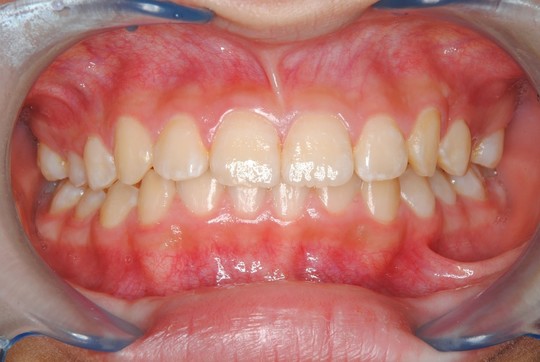

治療前

治療開始年齢 9

上下前歯部の歯並びが気になるとのことで来院されました。